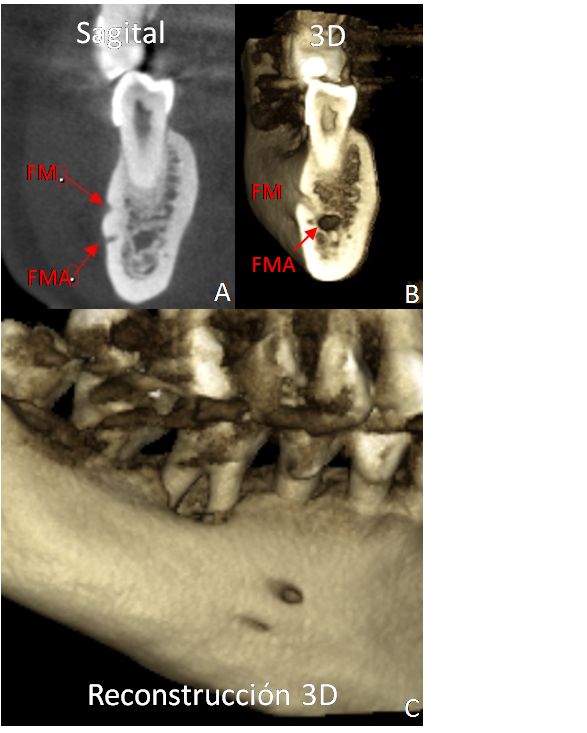

FORAMEN MENTONIANO ACCESORIO

Paciente femenina quien fue referida para estudio de Tomografía Computarizada Cone Beam (TCCB) de la unidad dentaria 46 con fines endodónticos, se observa como hallazgo, presencia de foramen mentoniano accesorio (FMA) en localización posteroinferior al foramen mentoniano (FM) del lado derecho (Figuras A,B, C).

Ocasionalmente se suele encontrar como hallazgo radiográfico, un foramen adicional, denominado FMA, localizado en la cara externa del cuerpo de la mandíbula en posición  posteroinferior o anteroinferior al FM. También se le conoce como foramen mental doble, foramen mental adicional, foramen mental múltiple, foramen mental accesorio o foramen mandibular bucal suplementario. Embriológicamente, se forma al mismo tiempo que el hueso mandibular, su frecuencia de aparición se ha reportado entre el 1-10% cuando es unilateral y del 0,4 al 1,2% si se presenta bilateralmente.

Es importante diferenciar un FMA de un foramen nutricio, el primero es una abertura en el hueso que se origina de la ramificación del canal mandibular, mientras que el foramen nutricio no se origina del canal y sus dimensiones son comparativamente menores.

El FMA puede ser observado en radiografías convencionales, tomografía computarizada y TCCB, sin embargo, desde que el tamaño del  FMA es usualmente menor a 1,00 mm, su identificación es difícil en un examen 2D. La TCCB provee de información detallada de las estructuras del complejo maxilofacial, el patrón del trabeculado óseo, reborde alveolar así como medidas esqueletales, permitiendo identificar variaciones anatómicas, es posible por lo tanto, evaluar en los planos axial, sagital y coronal la presencia de un FMA con la finalidad de orientar los procedimientos quirúrgicos a ser realizados en esta región y de esta forma evitar complicaciones como hemorragias, parestesia o disestesia, entre otras. Asimismo, se ha enfatizado la importancia de identificar un FMA antes del tratamiento de neuralgias, debido a que en pacientes con esta variación, la incompleta neurectomia del nervio mentoniano resulta en el fracaso del tratamiento.